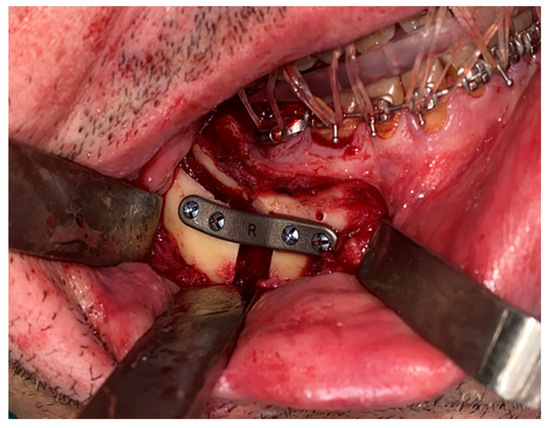

Next, an incision was made in the vestibular mucosa of the mandibular ramus, along the oblique line, extending from the first molar to the anterior region of the mandibular ramus. A mucoperiosteal flap was elevated to expose the external surface of the mandibular ramus, identifying the inferior alveolar nerve. The dento-osseous-supported cutting guide was positioned, and the BSSO osteotomy was performed using a reciprocating saw (Figure 5).

The same procedure was performed on the contralateral side. The mandible was positioned according to the preoperative plan and fixed with customized titanium plates (Figure 6). The final splint was used to perform a double check of the patient’s correct occlusion.

Figure 5. Placement of dento-osseous cutting guide for BSSO, aligned with the preoperative virtual plan.

Figure 6. Mandibular repositioning and fixation using custom-designed titanium plates, confirming intraoperative execution of the virtual plan.